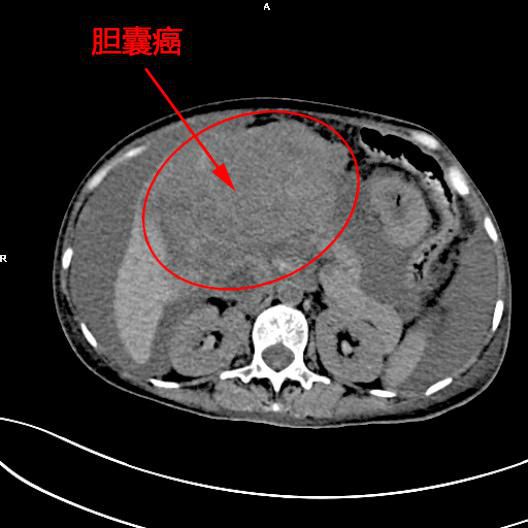

患者陳女士,57歲,汕頭潮南人,2個月前出現右上腹痛,在汕頭大型三甲醫院确診爲膽囊癌,因腫瘤爲晚期,已擴散至肝髒、十二指腸,患者放棄在汕頭治療,回家後自行采用中藥治療。近期右上腹痛加重,反複排黑便,遂來我院住院,診斷爲膽囊癌伴活動性出血。

入院後予泵入艾司奧美拉唑及生長抑素,輸注紅細胞等治療,仍有活動性出血,考慮到内科保守治療對膽囊癌出血無效,且該名患者的腫瘤巨大,多處轉移,已無法外科手術治療,隻能另辟蹊徑,于是李旭丹主任決定采用介入栓塞技術,并征得患者家屬同意。

5月11日下午,内三科主任李旭丹、影像科副主任胡志華上台施術。通過粵東領先的飛利浦DSA造影顯示,患者腫瘤供血血管豐富,膽囊動脈造影可見腫瘤染色明顯,有造影劑外溢,提示部分血管末梢有破裂出血現象,探查胃十二指腸動脈及腸系膜上動脈未見出血征像,豐富的血供使腫瘤能獲取大量的營養快速生長,血管末梢的破裂出血導緻患者反複黑便。